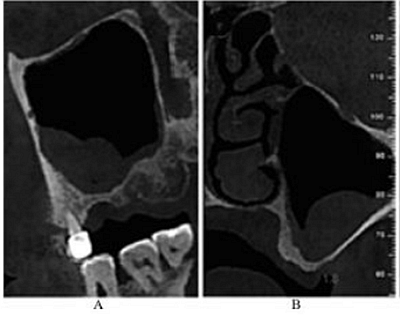

CBCT示:左側(cè)鼻甲水腫,左側(cè)上頜竇內(nèi)可見黏膜呈半圓形隆起,密度均勻升高,未見鈣化及明顯骨質(zhì)破壞;26牙剩余牙槽突高度(residual bone height,RBH)1.8mm,27牙RBH4.2mm,28牙RBH11mm,上頜竇頰側(cè)骨壁厚度約1mm(圖1)。

圖1 術(shù)前CBCT

注:A,矢狀面;B,26頰舌向切面;C,27頰舌向切面;D,28頰舌向切面。